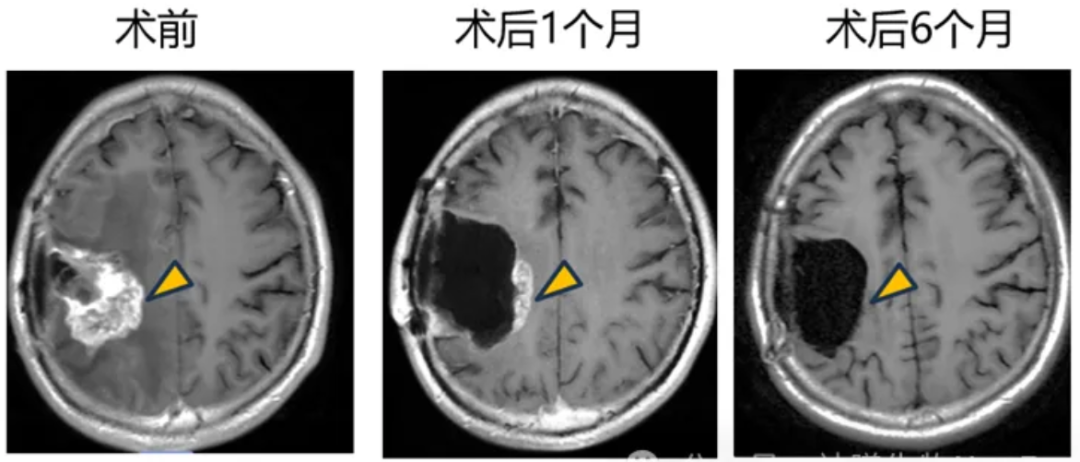

在瘤内注射患者中,观察到明确的治疗反应,靶病灶显著缩小超过 90%(图1)。

肿瘤切除+瘤腔内注射的1例患者,术后观察到肿瘤逐渐缩小并完全消退,达到影像学CR(complete response)(图2)。